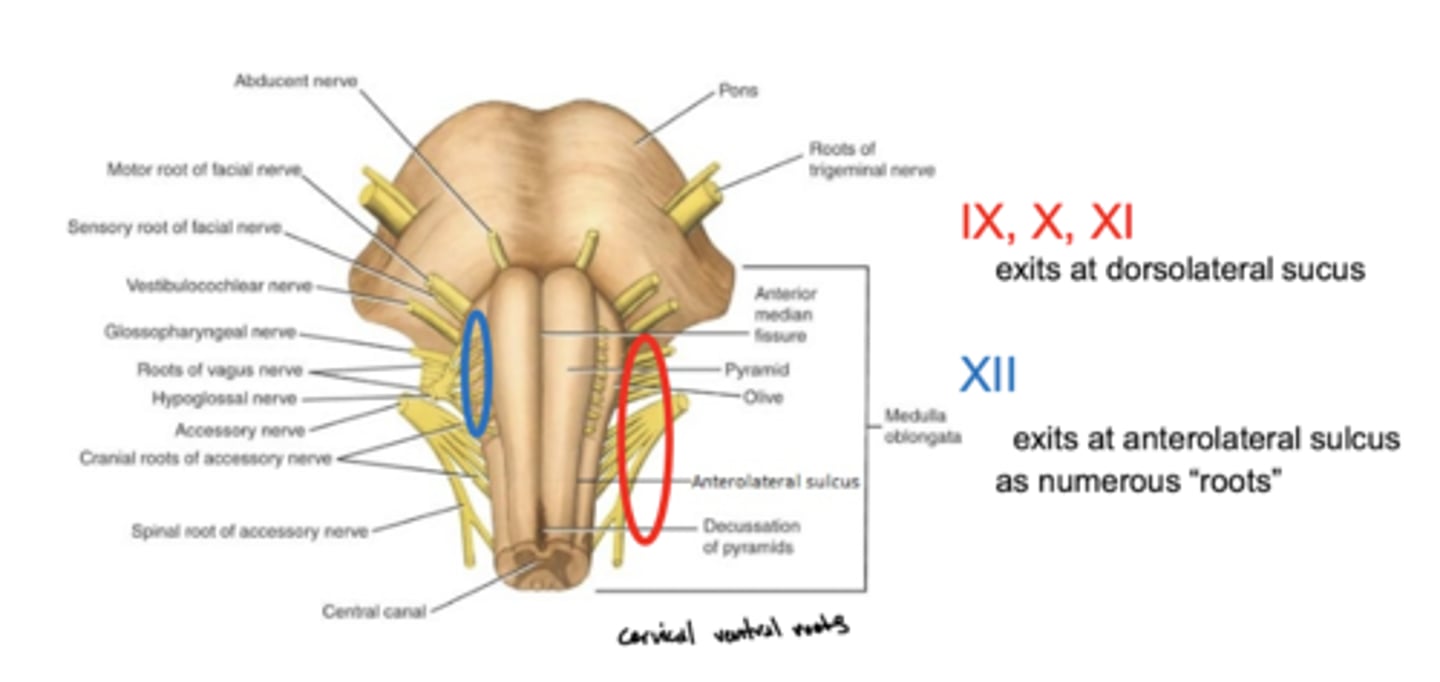

Where do CN IX, X, and XI exit the medulla oblongata?

exit the dorsolateral sulcus (

posterolateral sulcus)

3rd sulcus (counting medial to lateral) -- most lateral

Where does CN XII exit the medulla oblongata?

anterolateral sulcus -- as numerous roots

2nd sulcus (counting medial to lateral)